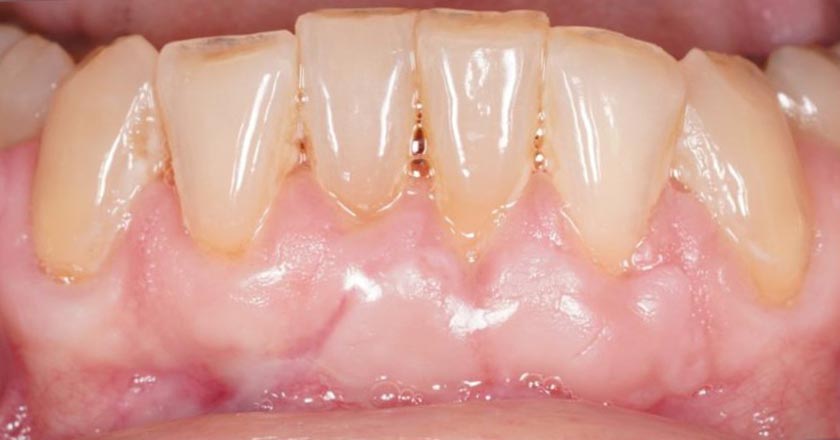

Gum Graft Lower - Before And After

Gum graft lower – before treatment